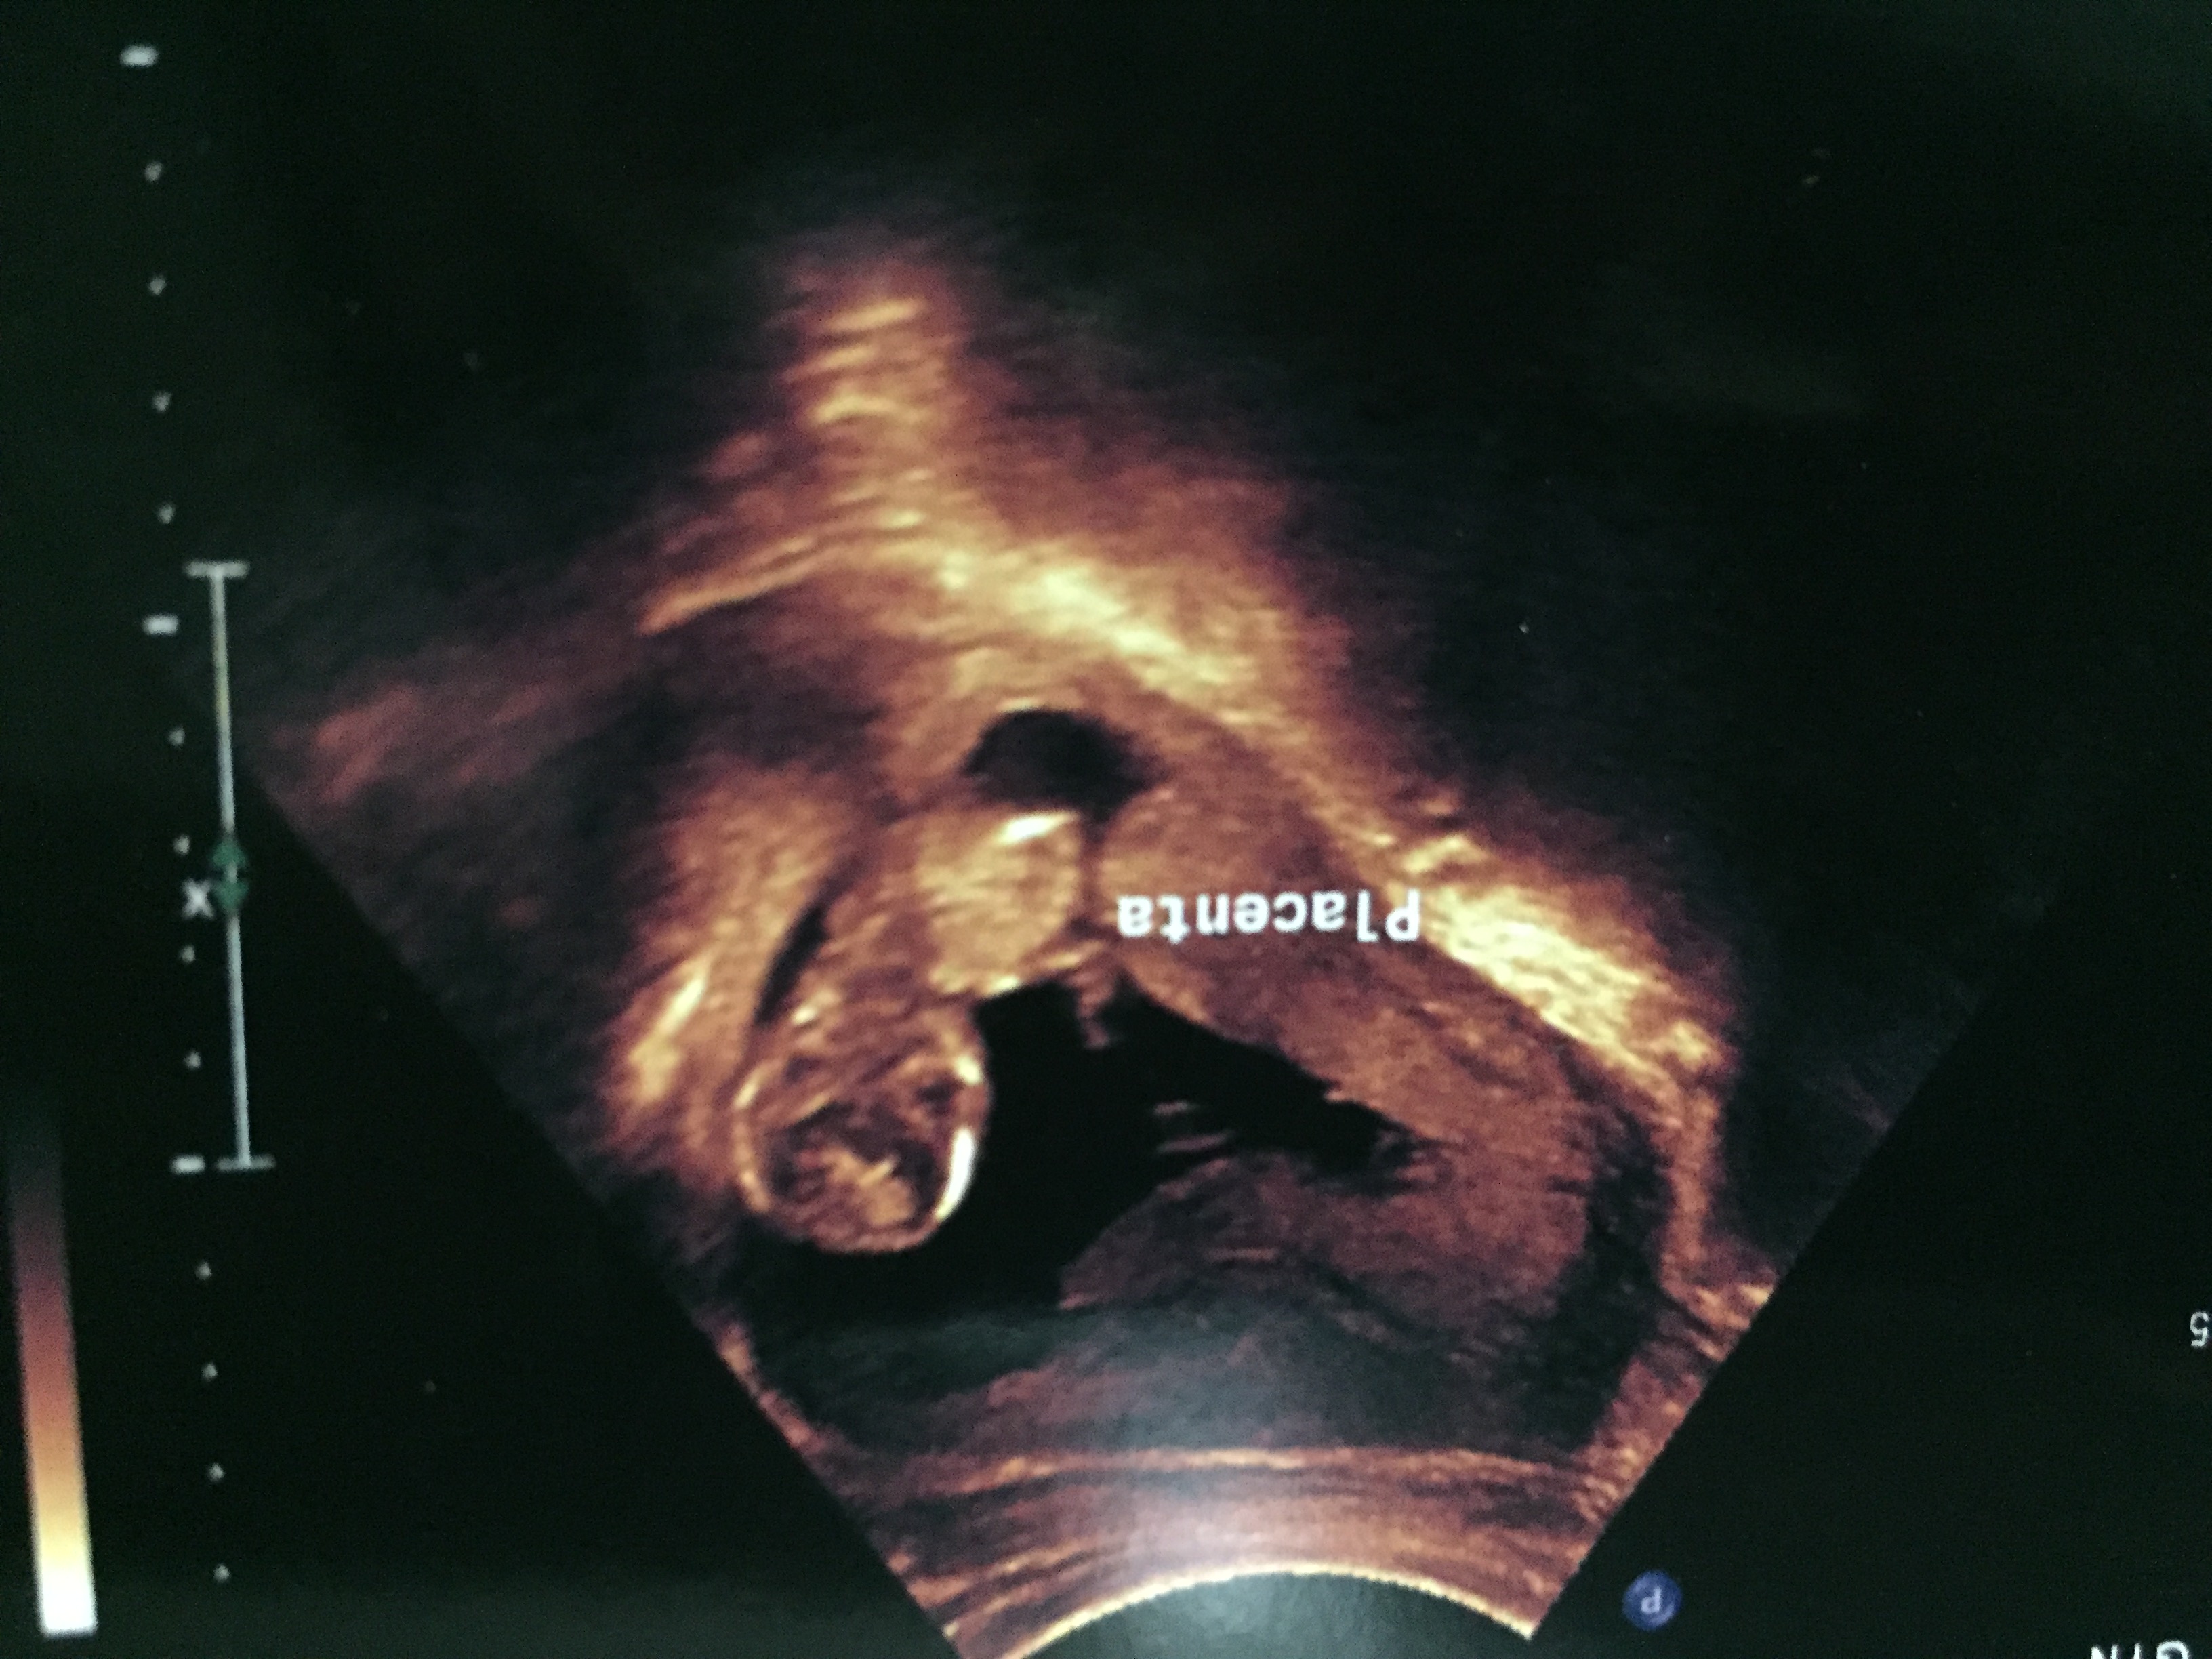

Attachment 39498Attachment 39499Attachment 39500Attachment 39501Attachment 39502

Guessing boy